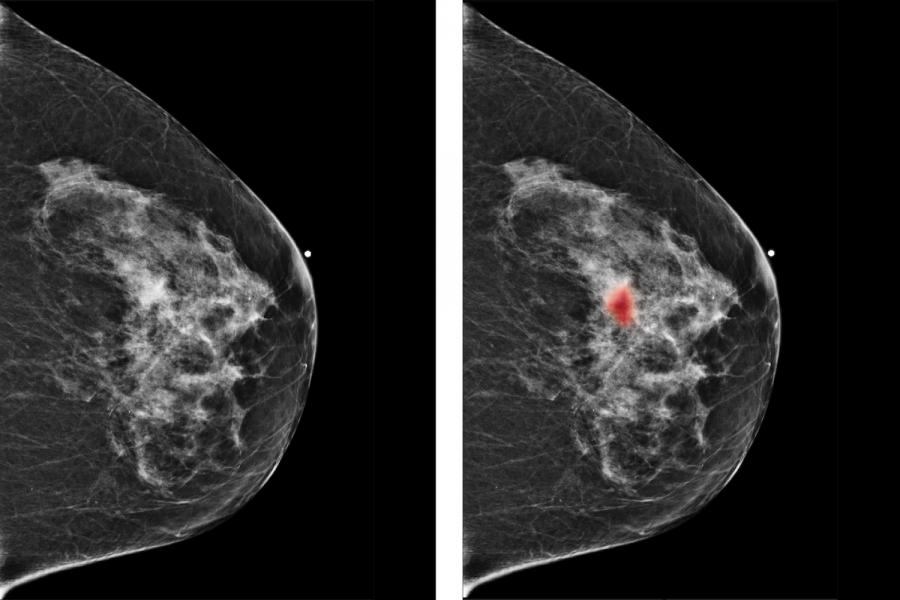

Deep Learning for Breast Cancer Detection

Our investigators develop deep neural networks to help radiologists detect breast cancer. This research involves several imaging modalities, including MRI and mammography. We tailor each algorithm to the relevant imaging method and design our networks to be human interpretable. In recent work, we have shown that neural nets can improve radiologists’ performance in breast cancer screening.